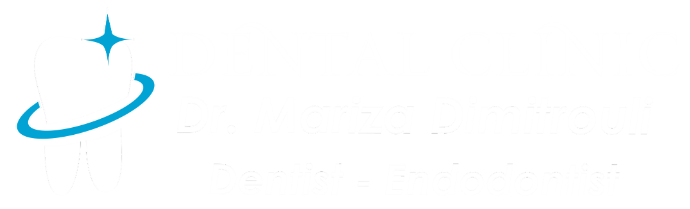

Root canal retreatment

BEFORE

AFTER